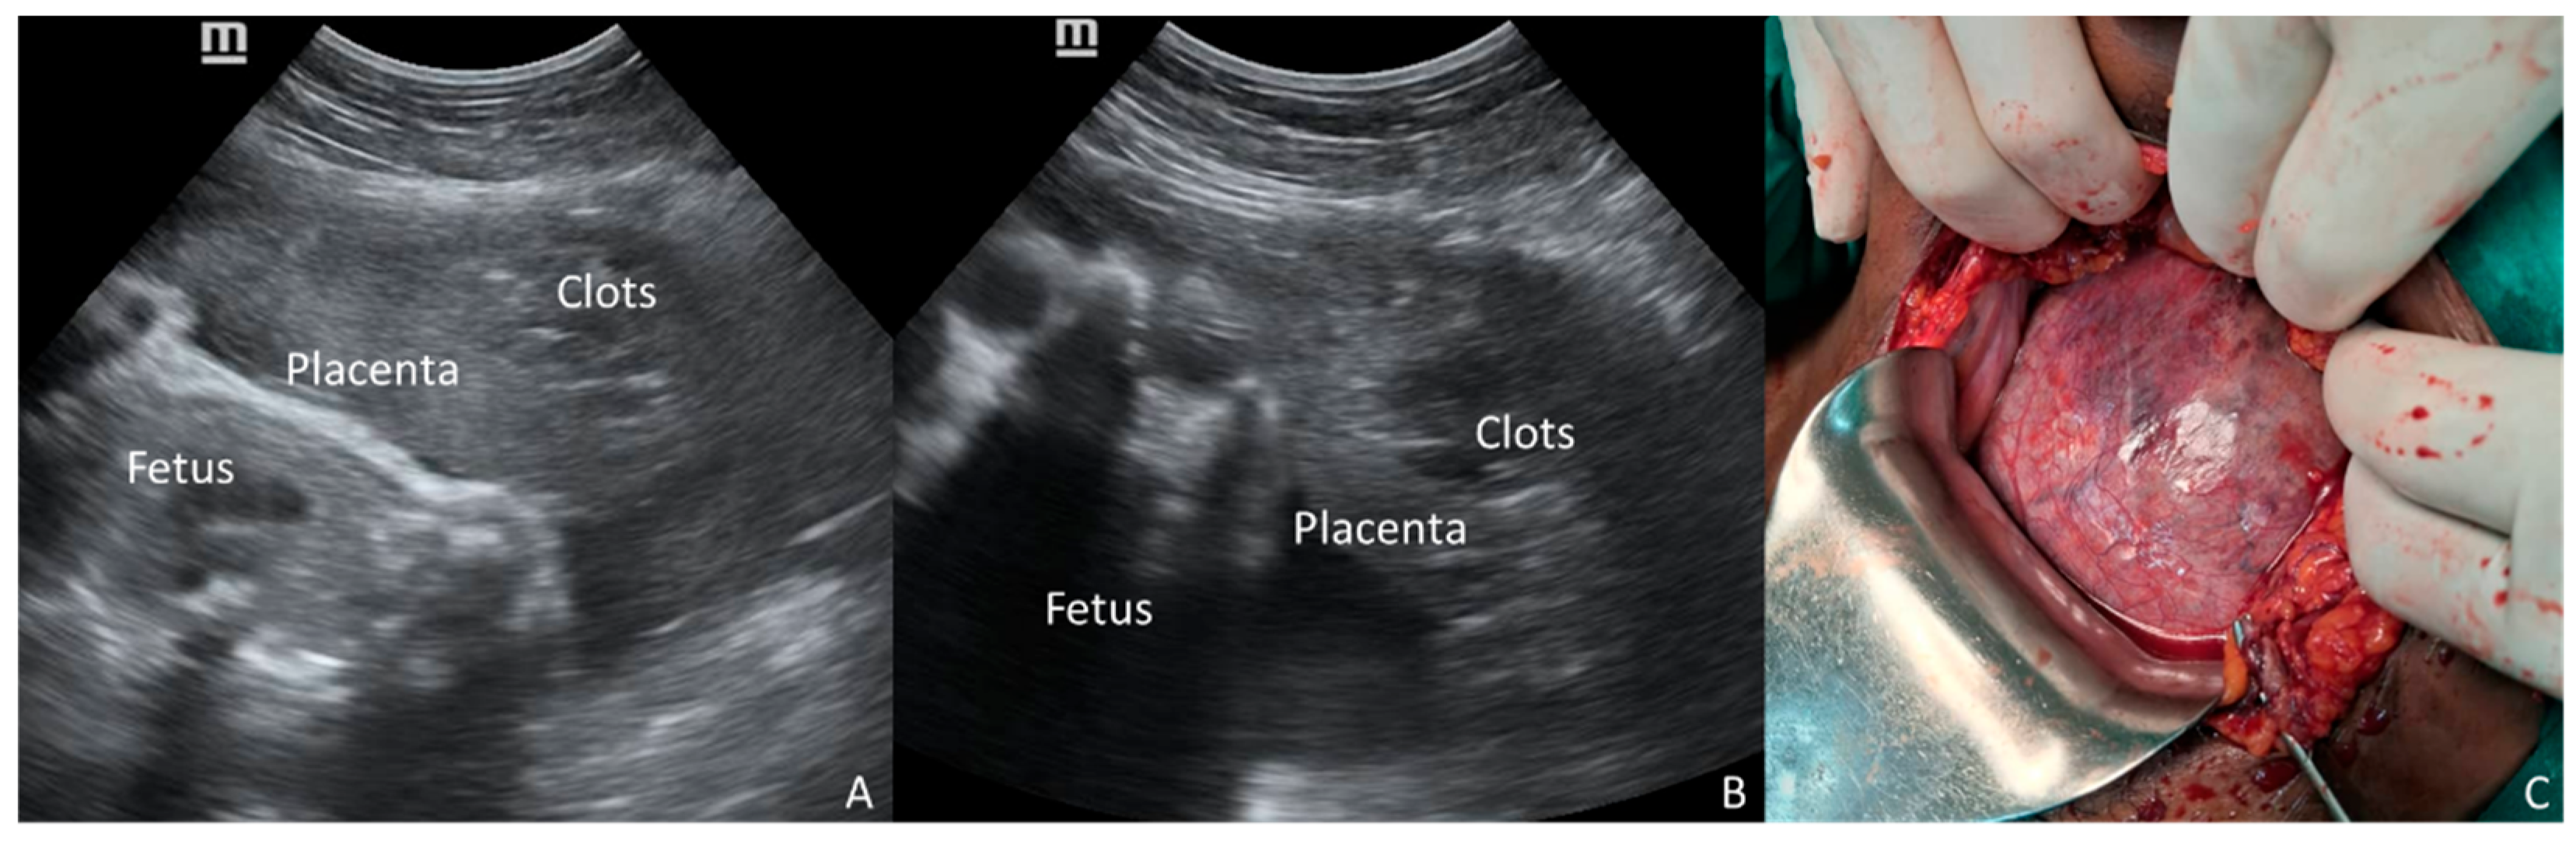

Figure 1.

A 28-year-old primigravid woman at 29 weeks of gestation was admitted with antepartum eclampsia. Fetal heart rate was regular upon admission, but POC-US (A) showed an unusual shape of the placenta, represented by a voluminous, round, inhomogeneous, and Doppler-negative mass, raising suspicion of concealed PA (arrows). Despite the proposal for emergency CS, the patient initially refused surgery, and extensive counseling with her family was required. During this period, fetal surveillance was intermittent due to the unavailability of continuous monitoring. After a delay of several hours, CS was performed, and a massive PA was confirmed; the final outcomes were stillbirth and obstetric hemorrhage (800 mL of retroplacental clots, B).